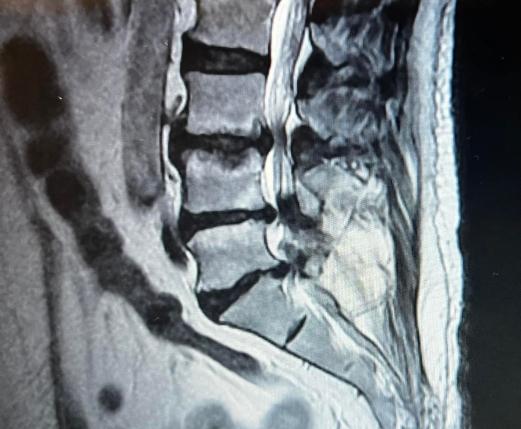

• MICROCIRUGÍA DE HERNIA DE DISCO

• CIRUGÍA DE HERNIA DISCAL CERVICAL

• DISCO ROTO

• CIÁTICA